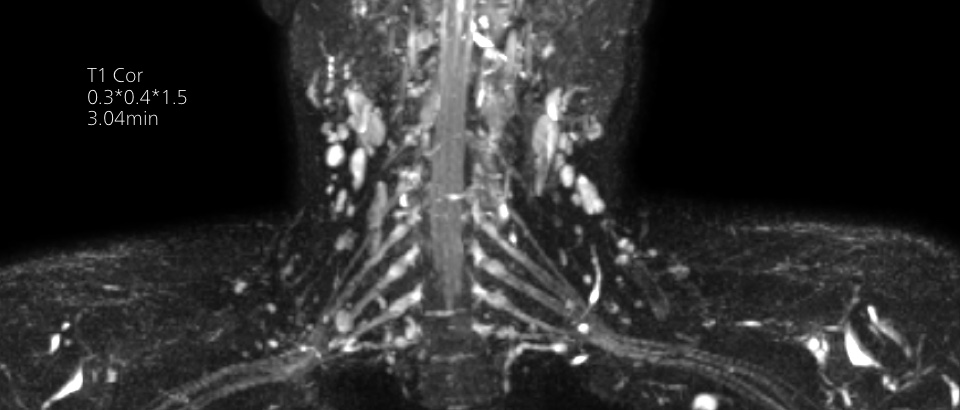

Imagenología de diagnóstico de alta calidad

Nuestras bobinas Breeze ultraligeras aportan versatilidad y crean imágenes uniformes de alta calidad para cualquier anatomía.

Imágenes de calidad para diagnósticos de calidad

Nuestras bobinas Breeze ultraligeras aportan una versatilidad extraordinaria para obtener imágenes de anatomías complejas y las articulaciones más pequeñas. Además de la excepcional calidad de imagen, ofrece un gran campo de visión de 55 cm y un SNR premium.